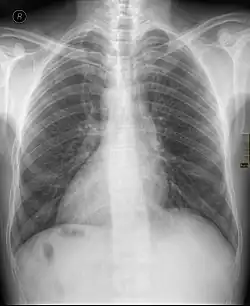

La dextrocardia es una situación en la que el corazón se encuentra en la mitad derecha del tórax debido a una causa de una alteración congénita.[1] Normalmente, el corazón se sitúa en la parte media del tórax, con su vértice o ápex inclinado hacia la izquierda; sin embargo, en esta malformación, ese orden es alterado y el corazón se ubica inclinado hacia el lado derecho del tórax. A menudo se asocia con otras anomalías del desarrollo y, en la mayoría de los casos, se diagnostica de forma incidental. Puede ocurrir por sí solo o puede ir acompañado de una inversión en la posición de otros órganos (denominado situs inversus totalis).[2]